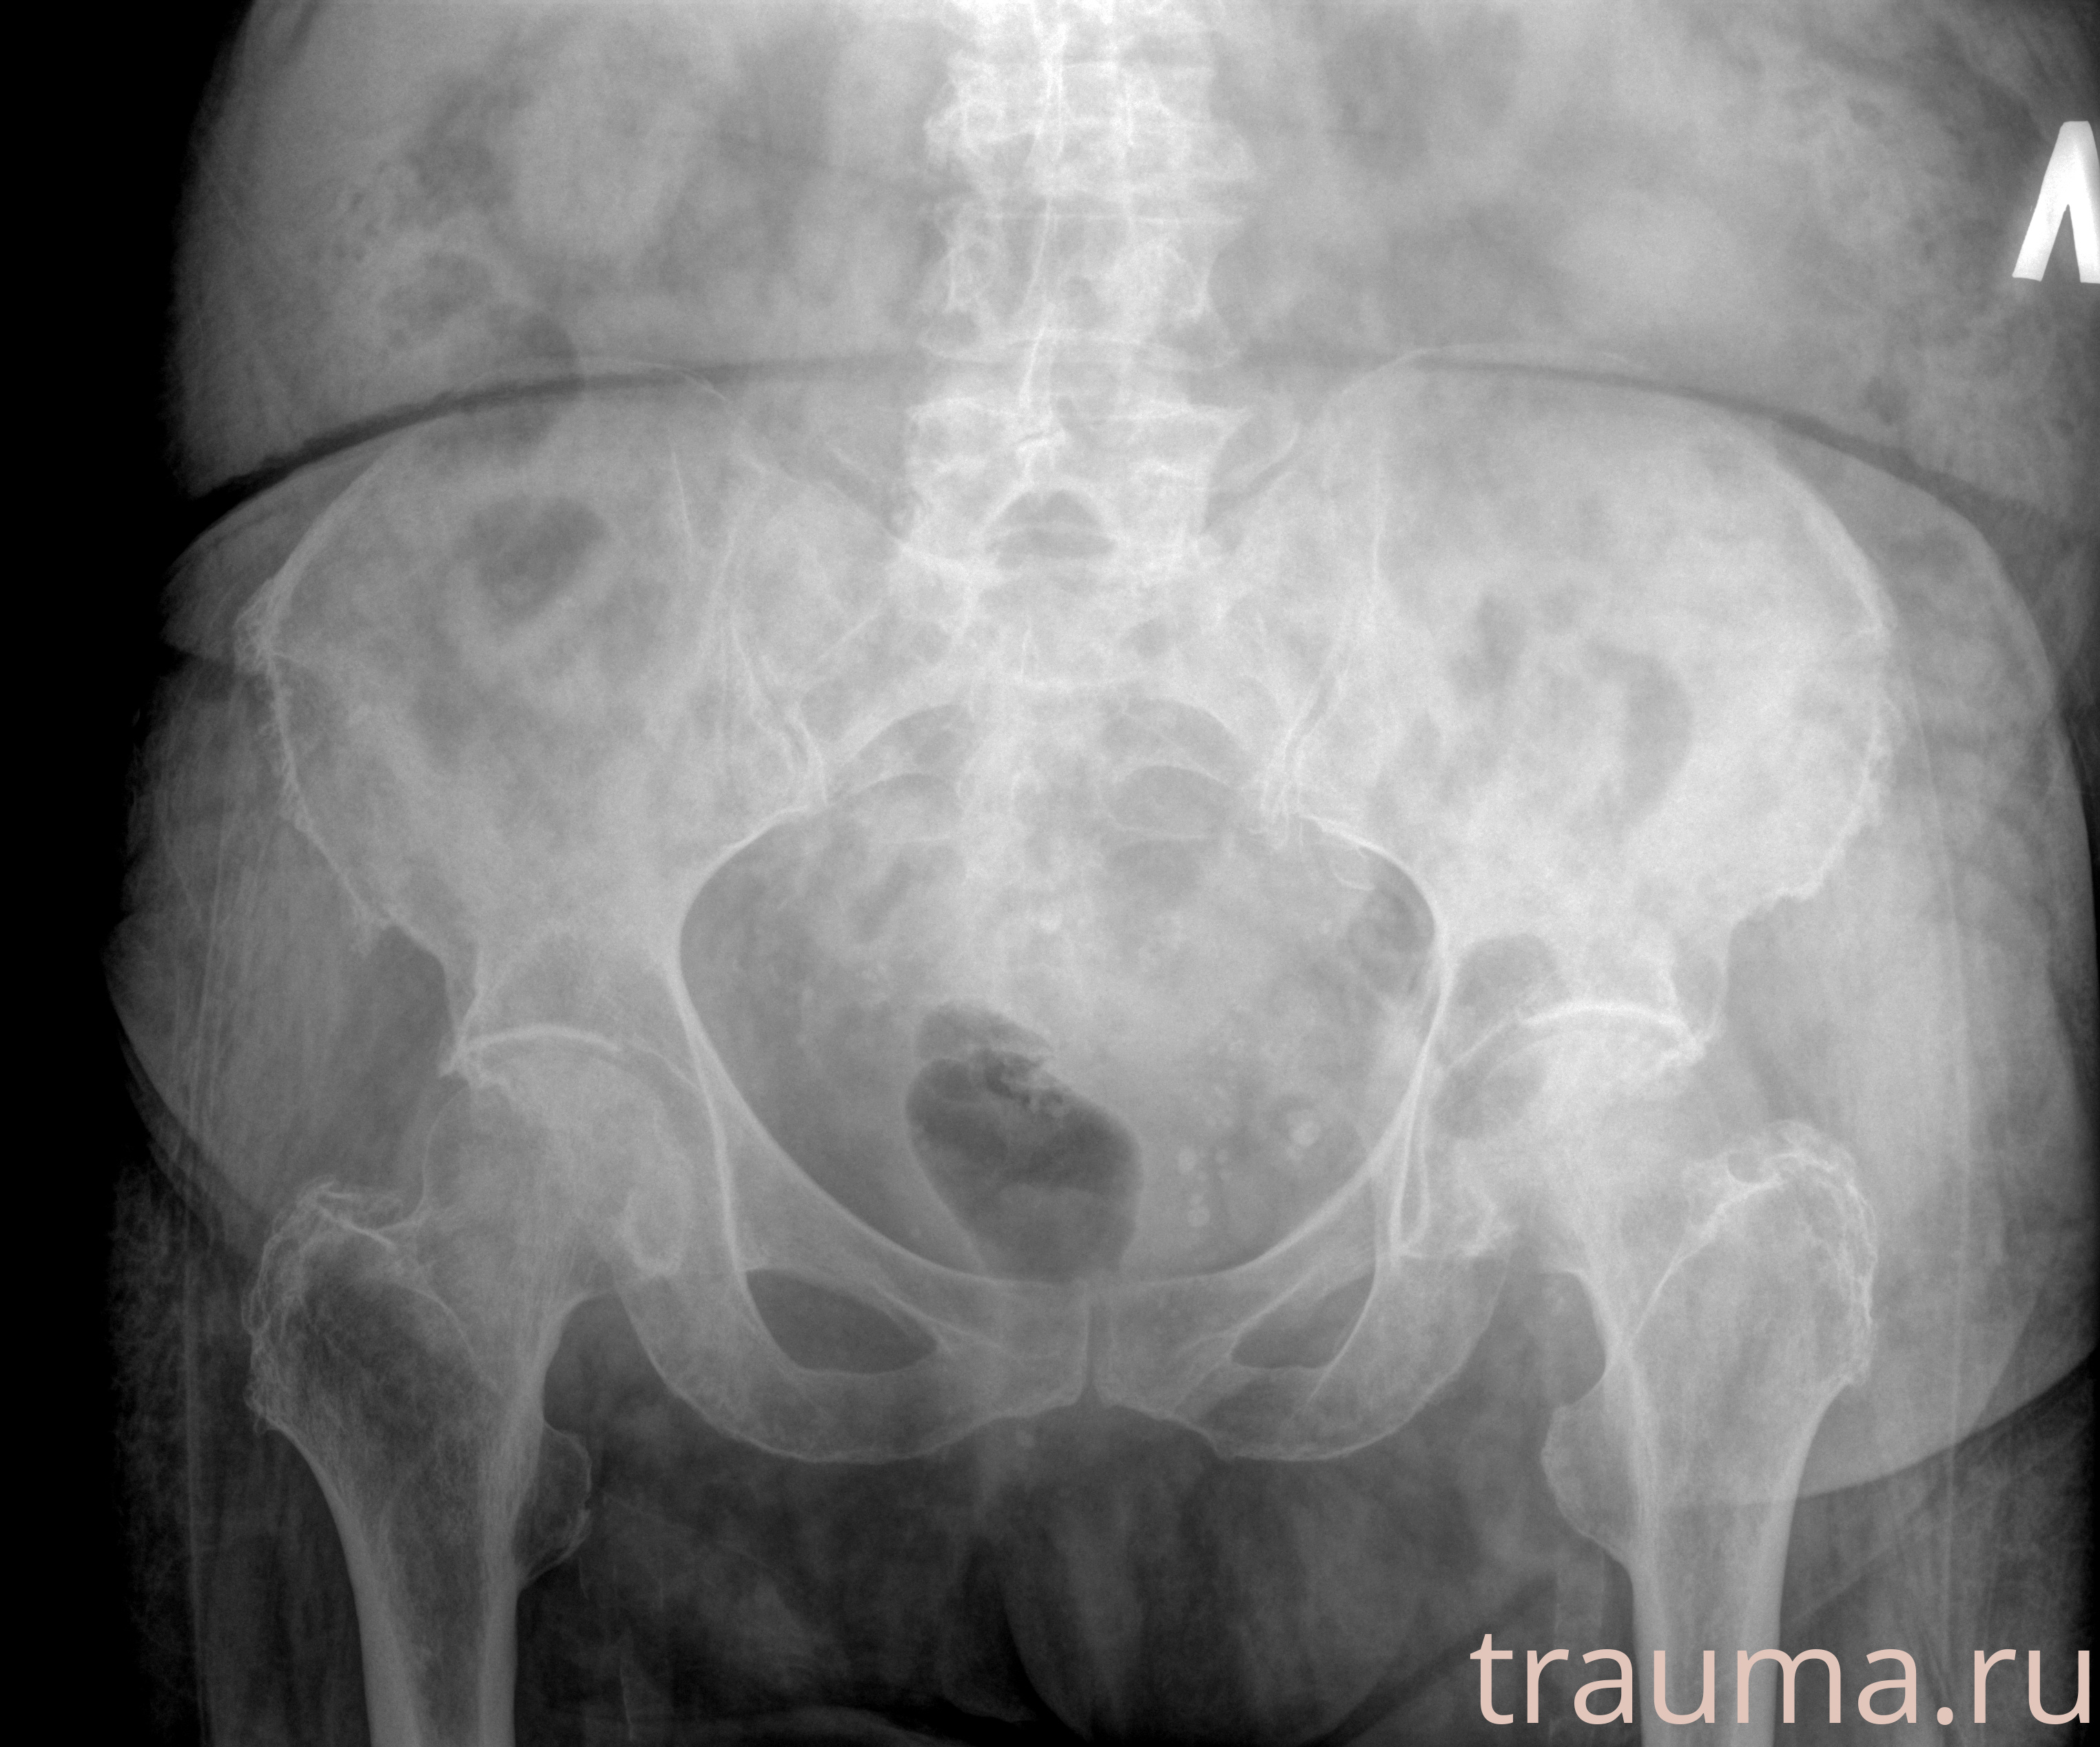

Рентгенограммы

Рентген на дому: по вашему адресу приезжает врач-рентгенолог, травматолог-ортопед с мобильным рентгеновским аппаратом, проводит диагностику травмы или заболевания, делает необходимые рентгенограммы, дает рекомендации по дальнейшему лечению. Получить качественные снимки в домашних условиях возможно благодаря уникальной методике, разработанной МосРентген Центром для института  Склифосовского

Яркость: 1   Контраст: 1   Инвертировать: 0 Увеличение: 1

Перетаскивайте мышь вверх/вниз для контраста, влево/право для яркости. Прокрутка колесом изменяет масштаб. Нажмите Сбросить для возврата к исходному изображению. При увеличении держите мышь в той области, которую хотите рассмотреть.